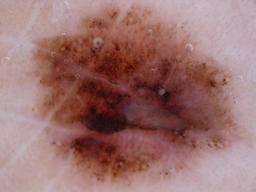

The BRAAFF-Annotated Acral Lesions Dataset (BALD): A curated set of dermatoscopic images of acral melanoma and nevi from various sources.

Müller C, Tschandl P, Rinner C, Kyrgidis A, Koga H, Moscarella E, Apalla Z, Di Stefani A, Kobayashi K, Lazaridou E, Longo C, Phan A, Saida T, Sotiriou E, Tanaka M, Thomas L, Zalaudek I, Argenziano G, Lallas A, Kittler H. The BRAAFF-Annotated Acral Lesions Dataset (BALD): A Curated Set of Dermatoscopic Images of Acral Melanoma and Nevi from Various Sources. J Invest Dermatol. 2025 Jan 17:S0022-202X(25)00021-1